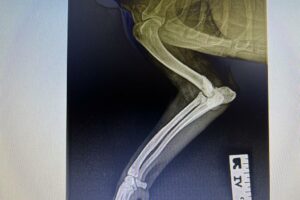

Rüde, Mischling, 3 Jahre, Vermittelt, stammt aus Italien, TierNr. 5213

Bullo

Mischling

3 Jahre

Rüde